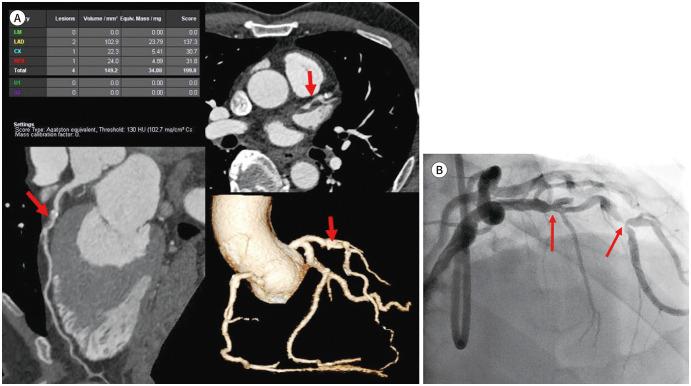

早期发现潜在的无症状冠状动脉疾病非常重要,因为心源性猝死患者通常不会表现出胸痛或运动性呼吸困难等症状。长期以来,冠状动脉CT血管造影(CCTA)作为无症状患者的筛查工具一直未被认可,因为存在辐射暴露风险。然而,对于CCTA在无症状健康个体或患者中筛查冠状动脉疾病(CAD)的实用性仍存在各种观点。本综述通过各种文献回顾,研究了冠状动脉钙化积分和CCTA作为无症状健康个体或患者CAD筛查试验的实用性。随着CT技术的发展,最近对无症状CAD患者进行了辐射剂量低于1 mSv的研究。在CCTA检查中,共有2.6%的无症状受试者被发现患有严重CAD(超过70%),得出的结论是,对CAD进行CCTA筛查在预测无症状人群未来CAD发生方面具有预后价值。然而,在当前的美国国立卫生研究院(NIH)SCOT-HEART 2研究完成后,或许可以确定CCTA是否适合作为无症状健康个体CAD的筛查工具。